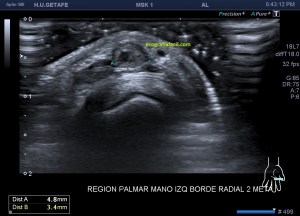

El paciente del caso que te expongo hoy como primer post del 2021 es un paciente de uno 40 años que nota desde hace un año un pequeño bultoma en la palma de la mano, en la región flexora en el eje largo del 2 dedo, a la altura de la articulación metacarpofalángica, ligeramente radial, viene referido del traumatólogo.

En mi interrogatorio habitual el paciente descarta traumatismo, no recuerda, ligero crecimiento sin dolor. Al tocar el bulto para localizarlo, lo primero que me llama la atención es que tiene pulso, muy evidente, es duro y muy pequeño, pero el pulso es muy evidente, no había coloración cutánea. El paciente ni el médico refirieron este dato superimportante (el latido) que dirigió el estudio absolutamente, como ves en la imágenes.

Escojo la sonda de ultraalta frecuencia, 18 mHz, y ajusto los parámetros para realizar un estudio con la intención de encontrar algo muy superficial, por supuesto, gran cantidad de gel, nada de presión, apoyo levemente el transductor.

Hallazgos:

1

En esta primera imagen me encuentro, primero, un estructura heterogénea, redonda, ligeramente ovalada con un centro anecoico y un halo grueso e hipoecogénico.

Lo segundo es delimitarla bien, tener bien estudiada la anatomía de referencia, imagen 2, respecto de la ecoestructura patológica y su propia ecoarquitectura. Por supuesto aplicamos el protocolo de referencia, localización, estudio, medición y vascularización que hoy ves resumido en estas 5 imágenes ya que el estudio lo enfoqué en el estudio de algo vascular.

2

La anatomía, tan importante siempre, buscando la relación, sobre todo, con el tendón al que claramente esta lesión no pertenecía ni afectaba.

3

El corte en eje largo como te indica el pictograma es muy importante, en teoría debería haber encontrado una estructura redondeada en eje corto y tubular en eje largo, como debiera corresponder a esta lesión vascular, pero los hallazgos no arrojaron dicha imagen.

Demostré el pulso en ambos ejes, pero no pude comprobar la estructura tubular en longitudinal…el motivo, el tamaño de la estructura y su gruesa pared que puedes apreciar en ambos ejes y que correspondía a una incremento de la pared del propio vaso, vaso que se encontraba parcialmente trombosado por este crecimiento de su pared, habitual en estas lesiones post traumáticas, donde el propio vaso sangra y esa sangre se colecciona alrededor el mismo.

4

Se demostró lo que ya presentía, que era la vascularización típica de un vaso, vaso que resultó ser uno de alto flujo, y  te explico…cuando estudiamos una malformación vascular por ecografía, podemos encontrarnos malformaciones de bajo flujo, las venas, de alto flujo, arterias o mixtos de ambas.

5

En la imagen 5 ves el típico aspecto de un vaso de alto flujo, lo normal, ya que tenía latido. Vas a ver dicho espectro con aspecto de picos y valles muy marcados, el sonido también es diferencial, puedes ver el doppler espectral y escucharlo. Su sonido y su aspecto es distinto del de una vena.

En este caso debí usar una muestra, flecha amarilla de la imagen 5, lo más pequeña posible, ya que el vaso lo era igual, adaptaremos esta muestra al tamaño del vaso que quieras estudiar. si la muestra no es la idónea la lectura puede ser incoherente. La muestra es el tamaño del «roi2 que hará el registro de la zona a estudio. Te enlazo arriba para que revises nociones básicas de doppler en post anteriores, también puedes consultar el índice del blog al final de este Post.

En este vídeo puedes ver como en la imagen 2D  como late la estructura, y como con el doppler color la vascularización es evidente. Puedes estudiarlo con Triplex, en el enlace a instagram ves como se estudia la lesión con una técnica de la que ya te he hablado más veces, donde puedes ver el doppler color y el espectral a la vez, eso sí, consumieno muchos recursos del equipo.

El diagnóstico final del radiólogo fue psudoaneurisma de la arteria palmar del segundo dedo.